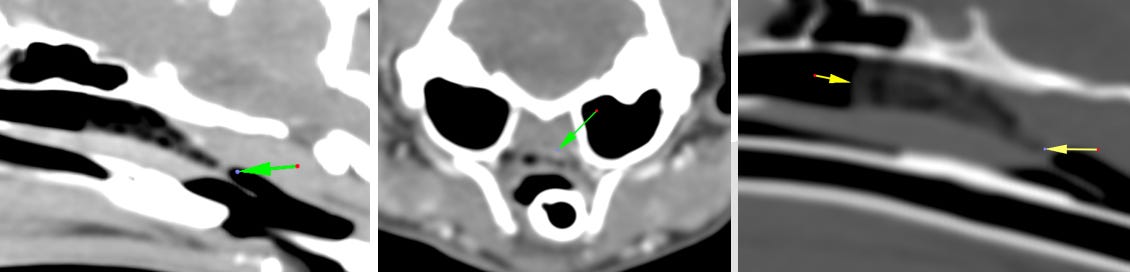

Realizamos imagen avanzada del cráneo, donde podemos observar en el aspecto caudal de la nasofaringe una estenosis grave con pérdida casi completa de la luz (flechas verdes).

Oralmente a esta estenosis se observa leve aumento de espesor del paladar blando, además hay acúmulo de material hipoatenuante sin realce aparente mezclado con burbujas de gas (flechas amarillas).

La altura de la nasofaringe previo a la estenosis es de 6,6 mm, el ancho 1,1 cm. La distancia entre el paladar duro y la estenosis es de 3 cm.